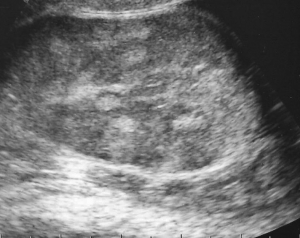

下の写真は精巣の超音波検査の画像です。正常な精巣は均一な画像(左)がみられますが、精巣炎・精巣上体炎の場合には異常に不均一なモザイク像が観察されます。